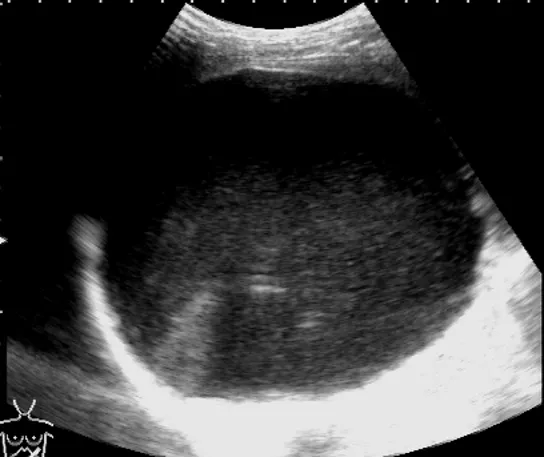

灰阶超声,脾囊肿,显示脾内一巨大的无回声囊肿,边界清晰。